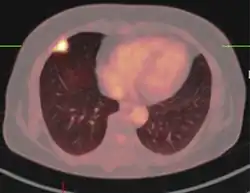

Imágenes

El aspecto de un tuberculoma en el diagnóstico por imagen puede variar en función de la composición y la edad de la masa. Pueden aparecer como lesiones no caseificantes o sólidamente caseificantes. Inicialmente, los tuberculomas aparecen hipodensos en la tomografía computarizada (TC) con un edema circundante significativo[27][28][29]

El "signo del blanco" es patognomónico de tuberculoma en la TC, con una masa nodular anular y calcificación central. El aspecto anular característico se debe a la falta de irrigación sanguínea en el núcleo necrótico central que se visualiza con el contraste inyectado[30]

A veces se observa una zona central hipodensa en lugar de calcificación. Al considerar otras posibles masas intracraneales en un diagnóstico diferencial, como la cisticercosis, el absceso piógeno y las lesiones neoplásicas, el tuberculoma puede identificarse por su mayor tamaño (>2 cm), edema y borde irregular.[31] [32] [33]

La resonancia magnética (RM) es otra modalidad de imagen útil para diagnosticar y caracterizar los tuberculomas, especialmente la necrosis caseosa sólida en la que se observan 3 zonas de intensidad variable[34]